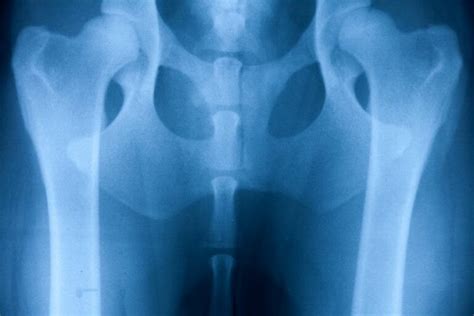

Diagnostikovanie dysplázie u nemeckého ovčiaka je nepostrádateľné pre zabezpečenie adekvátnej veterinarnej starostlivosti. K identifikácii dysplázie aplikujeme rozmanité diagnostické metódy. Primárne sa uprednostňuje röntgenové vyšetrenie. Táto technika nám poskytuje detaile o stave kyčľových kĺbov. Pri fyzikálnom vyšetrení odborník hodnotí pohyblivosť a stabilitu kĺbov vášho psa. Tieto testy sú zásadné pre presnú diagnostiku zdravotného stavu psa.

Dysplázia bedrového kĺbu sa diagnostikuje röntgenovým vyšetrením. Aby bolo možné röntgenovú snímku bedier optimálne posúdiť, musí byť táto vždy vykonaná v anestéze v štandardizovanej polohe. Narkóza psa je nevyhnutná na uvoľnenie svalov, a aby pri polohovaní na snímku nepociťoval bolesť. Veterinárny lekár môže pomocou röntgenových snímkov vyhodnotiť závažnosť dysplázie bedrového kĺbu a posúdiť zmeny v bedrovom kĺbe. Zásadným hodnotiacim kritériom je „Norbergov uhol“, ktorý sa určuje dvoma líniami medzi stredmi oboch hlavíc stehennej kosti a predným okrajom kĺbovej jamky. U psa bez DBK ochorenia by mal byť uhol väčší ako 105 stupňov.

Pri výbere chovných zvierat sú potrebné určité kritériá na vyhotovenie röntgenových snímok a ich hodnotenie. U niektorých plemien, v niektorých krajinách alebo pri odborných posudkoch, je potrebný ďalší röntgen s roztiahnutými stehnami a nadvihnutými členkami (tzv. „žabí snímok“), pretože zmeny okraja kĺbovej jamky a stehenných kostí sú tak lepšie viditeľné. Rozdelenie chovných zvierat sa uskutočňuje podľa predpisov Medzinárodnej kynologickej federácie F.C.I.